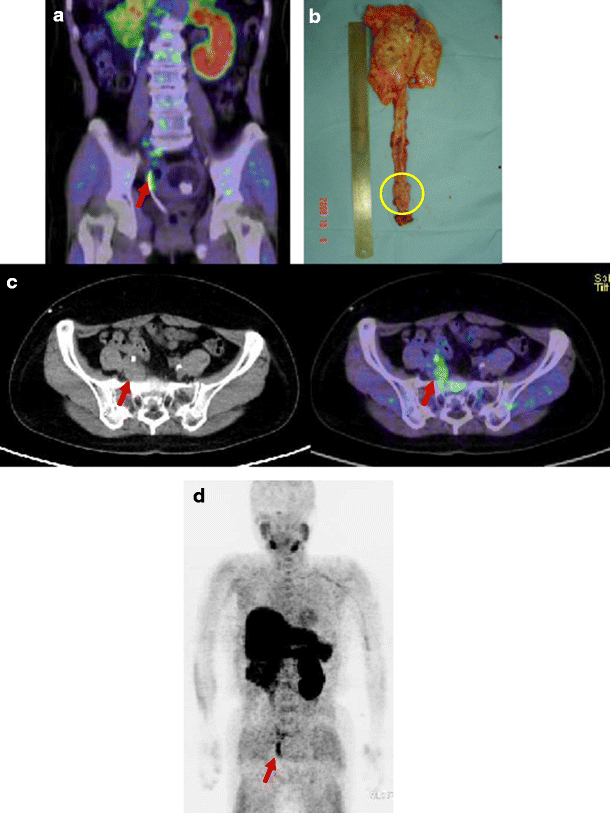

Urothelial carcinoma of the right ureter in patient 11. a Choline PET/CT images of the primary tumour at 10 min after injection (SUVmax 6.09). b Photograph of the primary tumour after resection. Circle tumour site. c Choline PET/CT images of the metastatic lesions at the right internal iliac lymph nodes at 10 min after injection (SUVmax 4.92). d Maximum intensity projection image. Arrows tumour sites. A catheter is inserted into the right ureter (a, d)